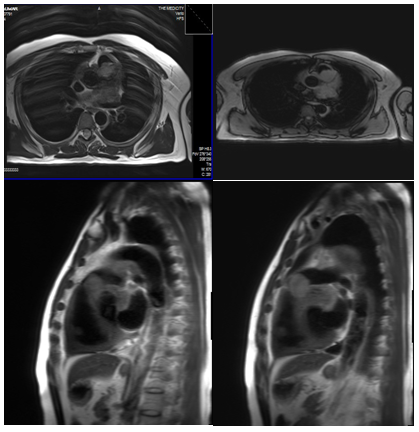

Transthoracic echocardiography showed oval homogenous mass - 2.6×1.9cm attached to lateral wall of MPA, protruding into the lumen, resulting in obstruction with peak gradient of 58mmHg,RV pressure overload with severe PAH, LVH with increased echogenicity. Cardiac MRI revealed (Figure 2-5) infiltrating mass lesion in relation to the ventricular outflow tracts, the antero-superior walls of the left atrium and basal left ventricle, the anterior basal interventricular septum and the aortopulmonary window. Circumferential thickening of the ascending aorta, aortic arch and the proximal descending aortic walls, encasement of the proximal coronary arteries and involvement of the pericardium and the pericardial fat was present.

Figure 2-5 Cardiac MRI revealed infiltrating mass lesion in relation to the ventricular outflow tracts.